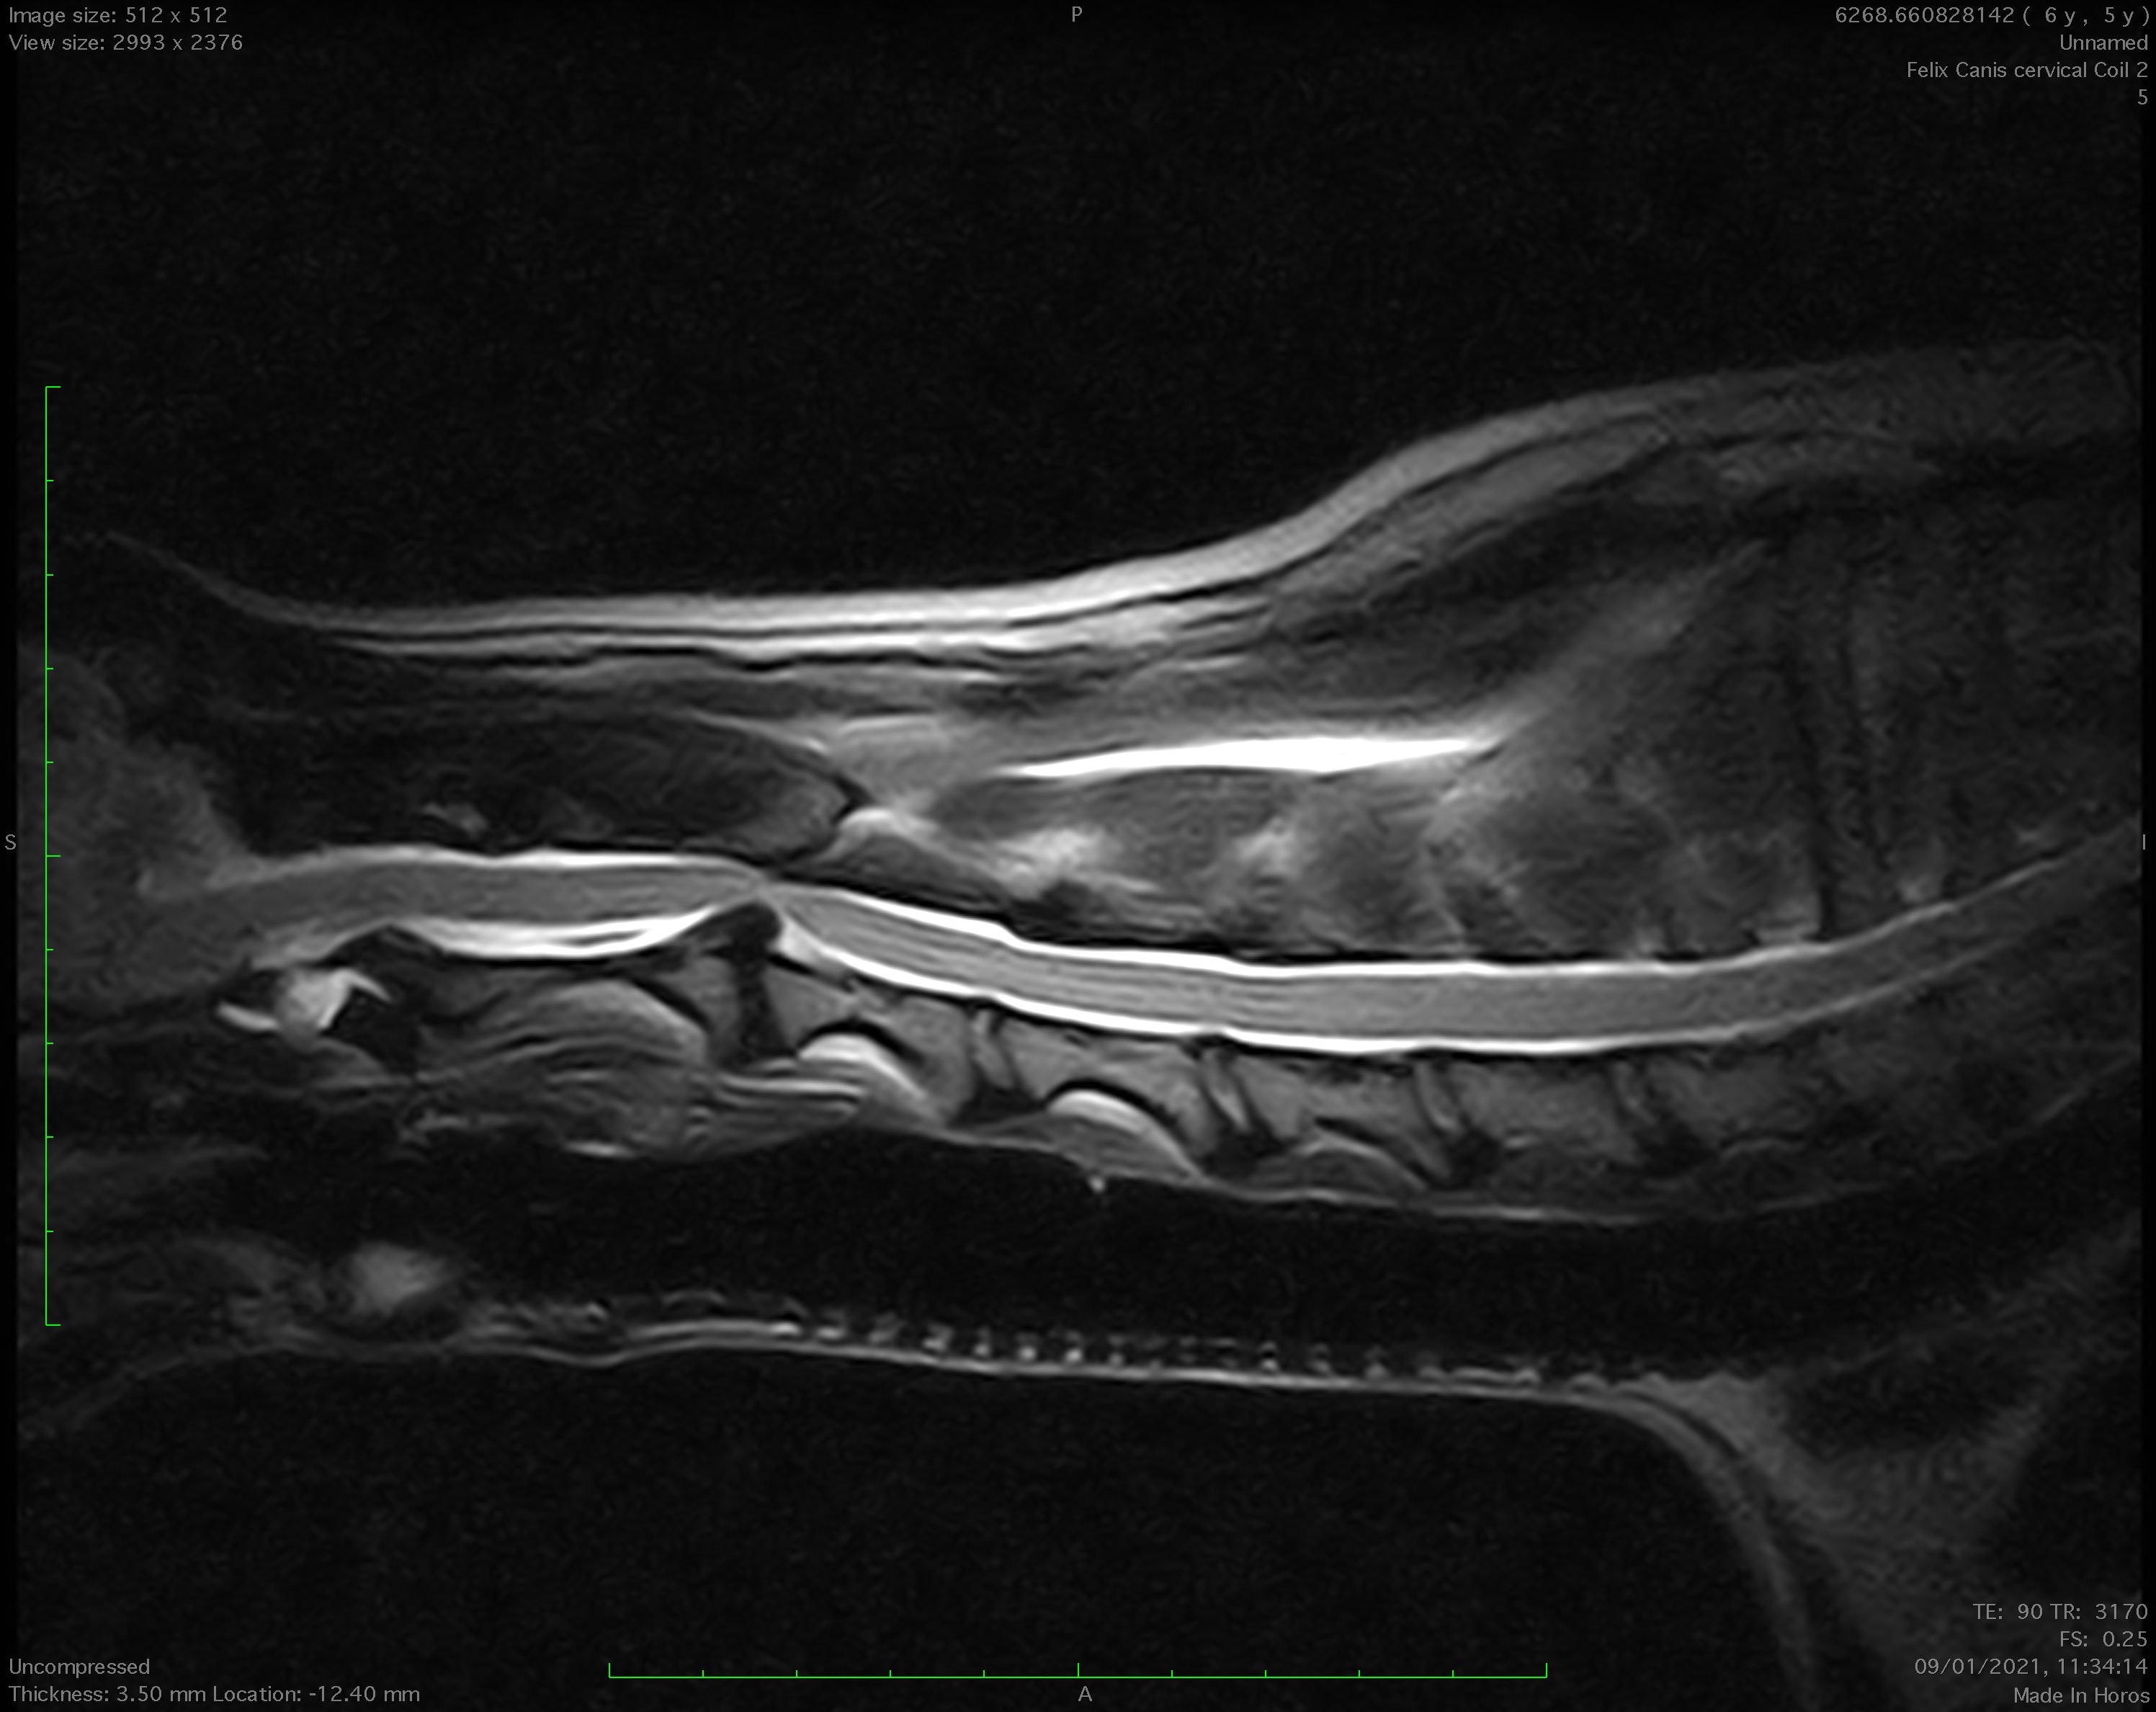

Récemment, notre centre s'est équipé d’une unité de résonance magnétique Esaote Vet MR Grande. C’est un modèle d’IRM vétérinaire ouverte composée d’un aimant permanent 0,25T d'un poids de 6,5 tonnes.

L’imagerie par résonance magnétique ou IRM est une technique très largement utilisée en médecine humaine depuis de nombreuses années. C’est un outil exceptionnel d’investigation non invasive d’une multitude d’organes ou zones, même si au départ son application principalement était dédiée à l’examen du cerveau et de la moelle épinière. A l’instar de la tomodensitométrie, plus connue sous le nom de scanner (CT scan), elle permet l’obtention d’images en coupes tridimensionnelles mais son mode de fonctionnement diffère. Contrairement au scanner qui utilise des rayons X, l’IRM n’utilise pas de radiation ionisante. Le principe de la résonnance magnétique nucléaire (RMN) est basé sur l’application de champs magnétiques. Cette caractéristique permet l’acquisition d’images avec un très grand contraste et en fait une des imageries de pointe à l’heure actuelle.